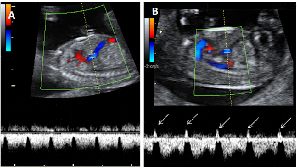

Ecografía Embarazo 4D Semana 12 - PRUEBAS DIAGNÓSTICAS